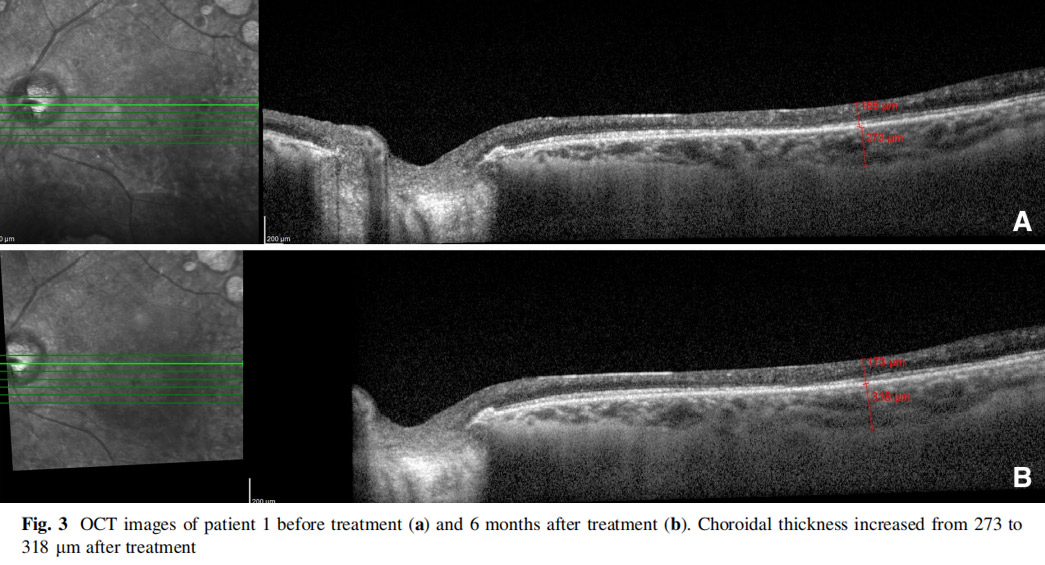

患者左眼接受AD-MSCs治療,6個月后視力提高至2米處數手指(CF)水平,視野中央島狀結構擴大,如圖1所示,左眼mfERG顯示改善(圖2),脈絡膜厚度從273μm增加至318μm(圖3),黃斑厚度和RNFL沒有變化。